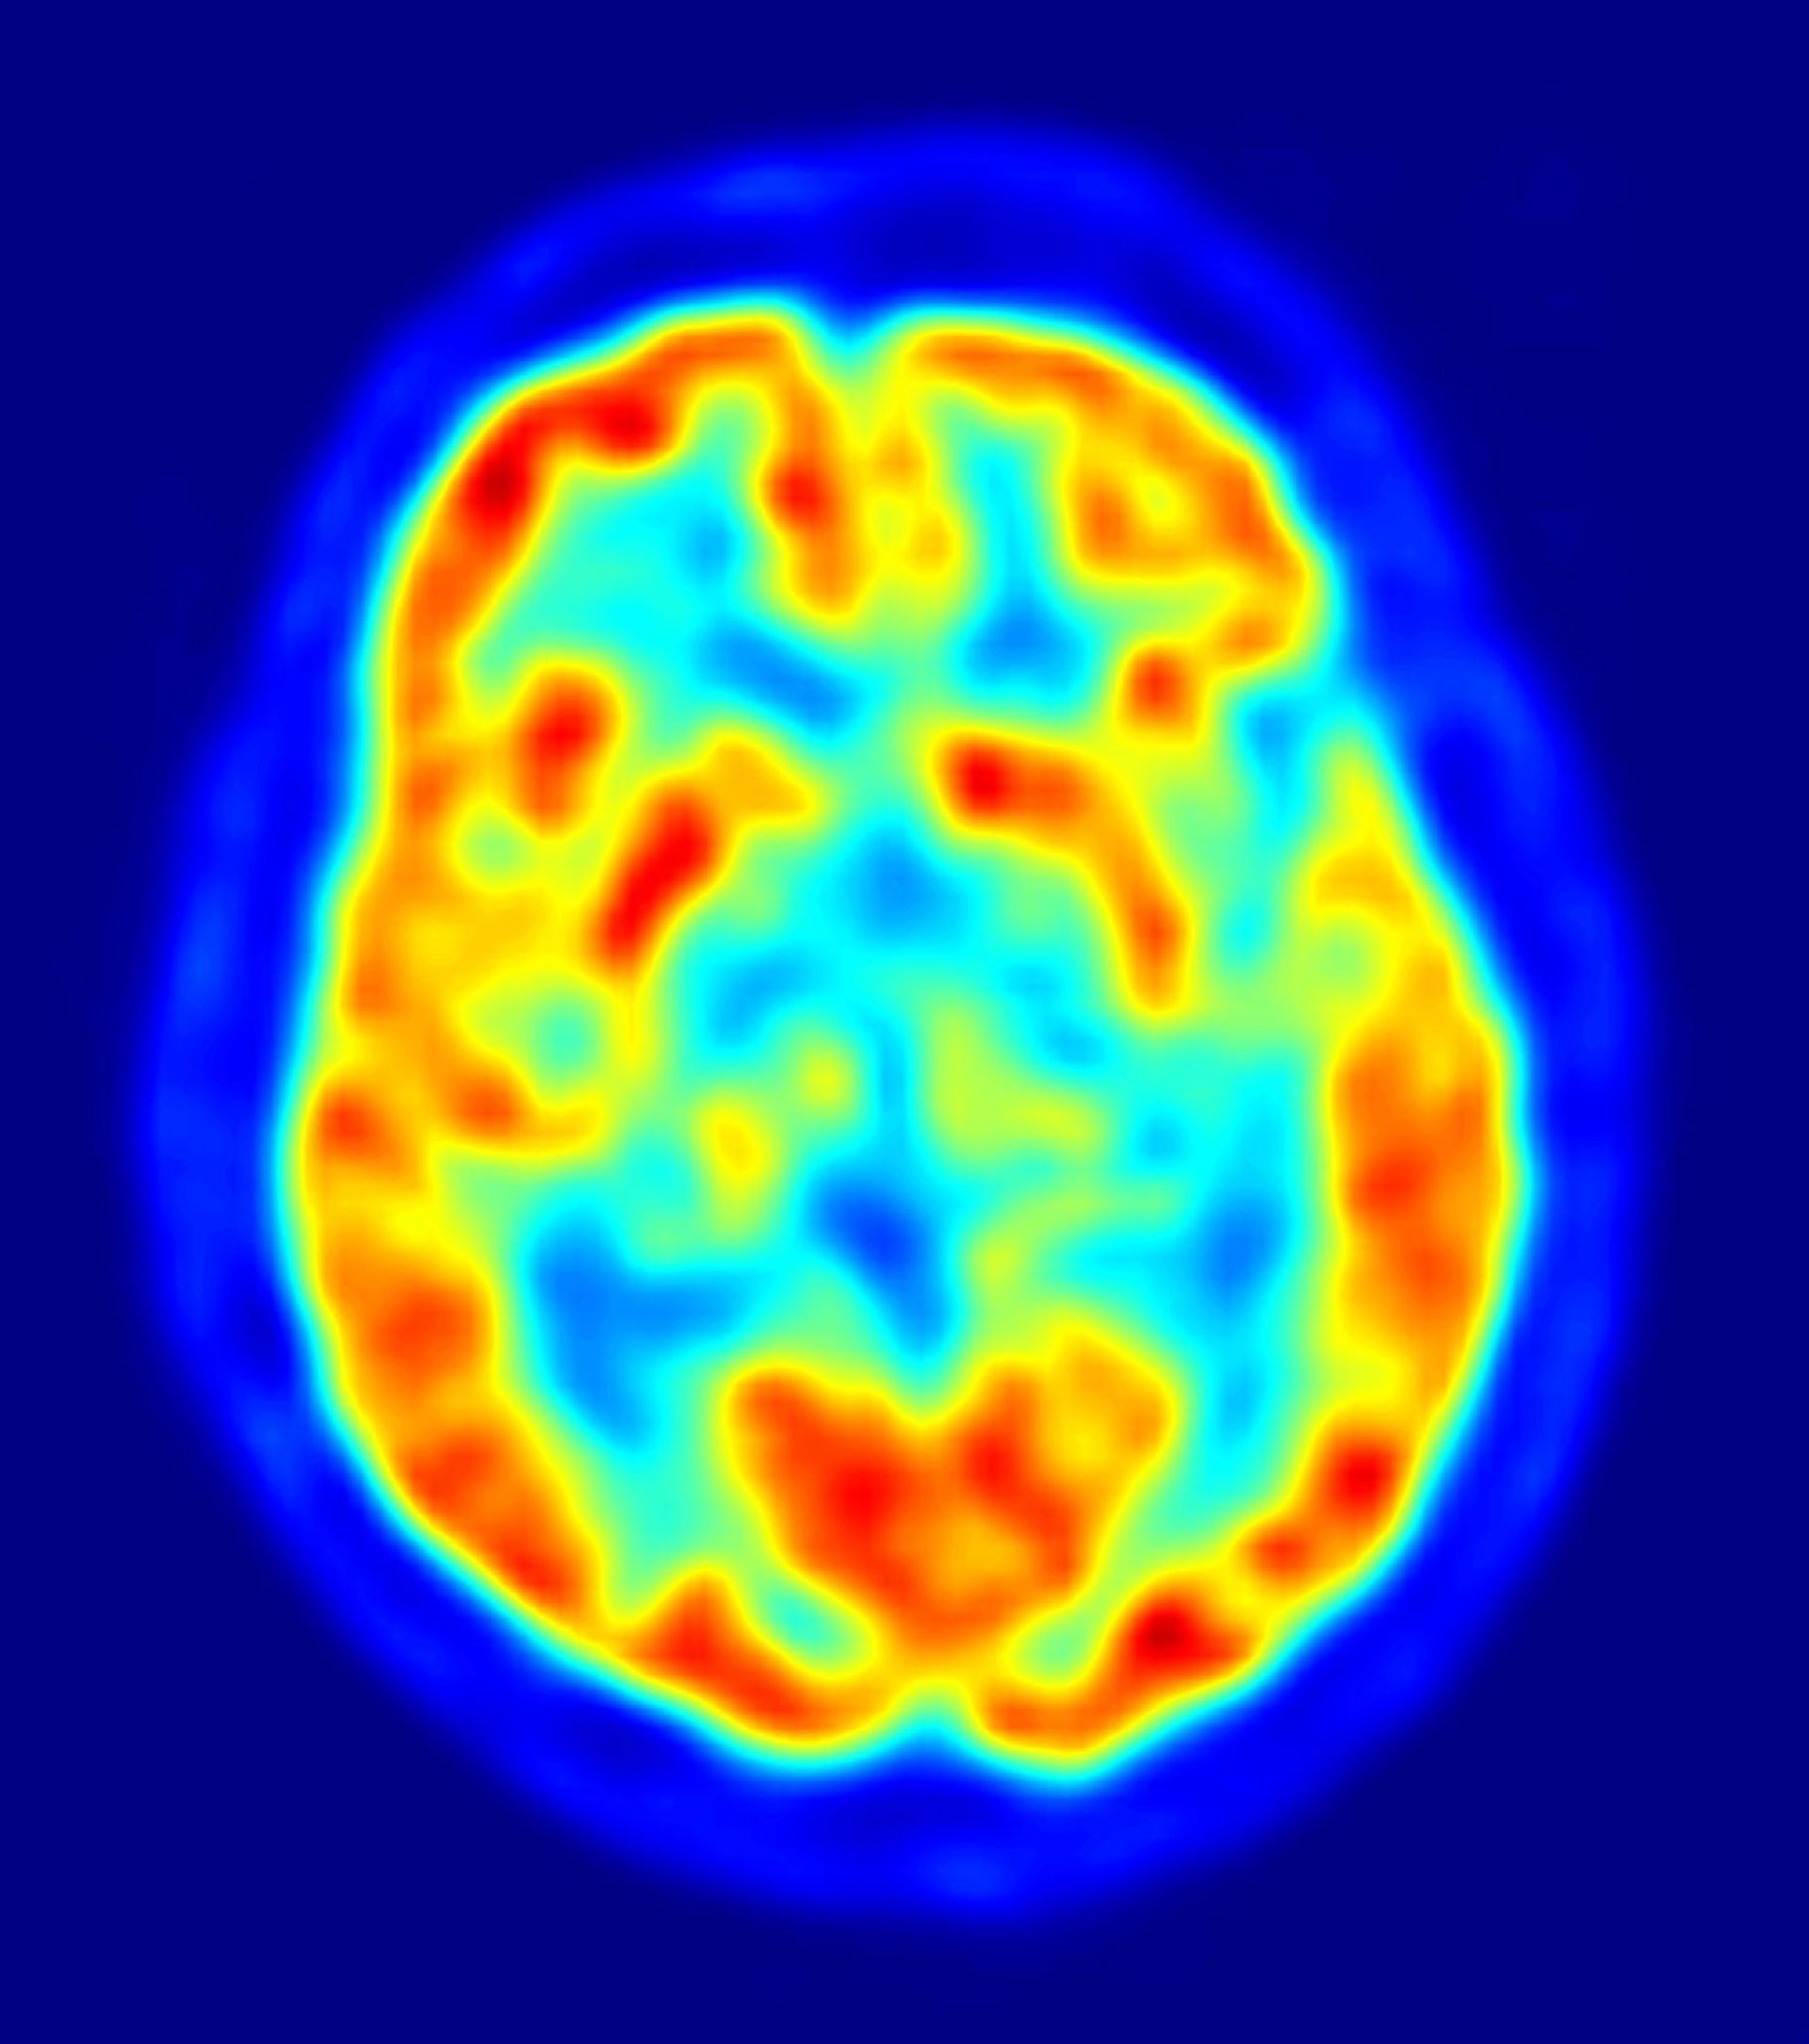

cerebro, recurso, neuronas

Investigadores de la Universidad de La Rioja, en colaboración con el Centro de Investigación Biomédica de La Rioja (CIBIR), están desarrollando un programa certificar diagnósticos a través del procesamiento de imágenes biomédicas para perfeccionar su estudio de cara a la detección del Alzheimer.

Los investigadores de la UR plantean la corrección de un programa concreto como un enunciado de un teorema matemático, así buscan que este se produzca en cada proceso. Como se trata de conseguir un diagnóstico veraz, recuerdan que el programa debe obtener los mismos resultados de que los médicos, lo que tiene su complicación si se tiene en cuenta que el médico interpreta la imagen y el ordenador analiza píxeles sin ninguna estructura.